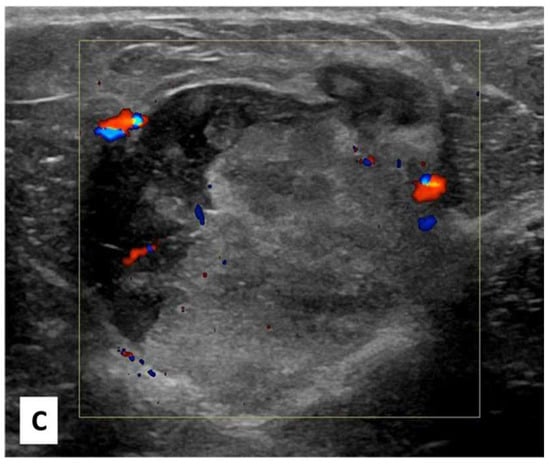

There was no indication of inflammation or swelling in either breast. A mammogram showed a large fat-containing oval-shaped lump with a circumscribed outline, and the mass in the upper outer quadrant of the right breast was approximately 9 cm from the nipple and measured 3 × 3.5 cm2 (Figure 2). However, mammography of the left breast showed nothing out of the ordinary. The subsequently targeted ultrasonography (US) revealed a heterogeneous isoechoic irregularly shaped solid mass that measured 3.3 × 3 cm2 and had eccentric cystic foci placed at the 9 o’clock position and approximately 8 cm away from the nipple (Figure 3). Differential diagnoses include phyllode tumor (PT) in addition to liposarcoma. The patient sought treatment at a tertiary hospital, where she underwent a right breast biopsy, and based on the findings of that procedure, a right lumpectomy without an axillary dissection was conducted. When seen under a microscope, the tumor was found to contain mature adipocytes, atypical spindle cells, and multivacuolated lipoblasts. All of these cell types were discovered to be embedded in a loose myxoid to fibrous stroma within the tumor itself. This information is provided by the pathology report. In addition, there were a significant number of regions that had pleomorphic cells, multinucleated, weird, enormous cells, and lipoblasts (Figure 4 and Figure 5).

Figure 3. Radial, anti-radial, and color Doppler right breast targeted ultrasound scan images. (A,B) shown at the 9 o’clock position and 8 cm from the nipple is a 3 × 3.3 cm2 superficial circumscribed irregular shape of a heterogeneous isoechoic mass with a small peripheral cystic component perpendicular to the skin; no posterior shadow; and no associated suspicious features (suspicious microcalcification or architectural distortion). (C) Color Doppler image of the mass showed peripheral vascularity.